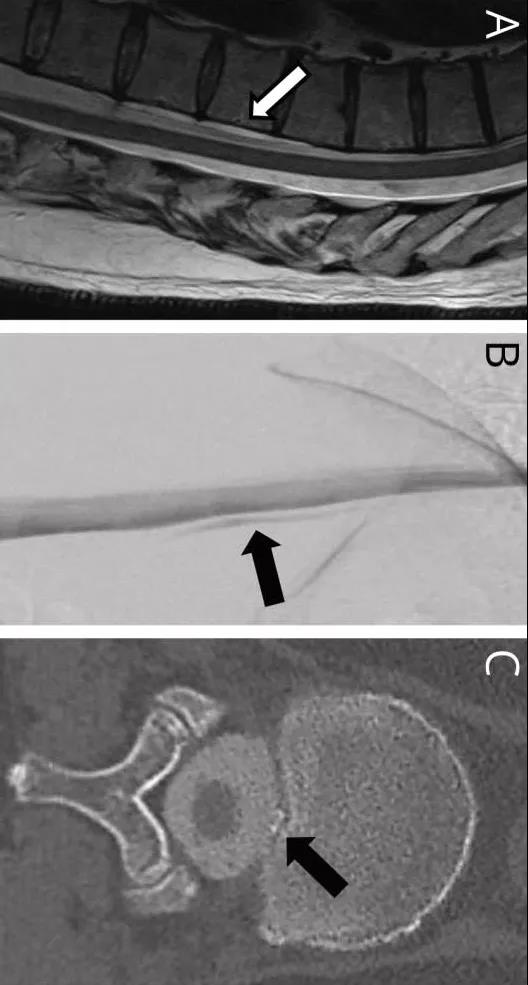

下图,T2加权矢状位脊MRI显示腹侧硬膜外CSF积液(A,箭头),DSM显示起源于T11-12水平的腹侧硬膜外CSF积液(B,箭头),DSM后CT显示小骨赘(C,箭头):